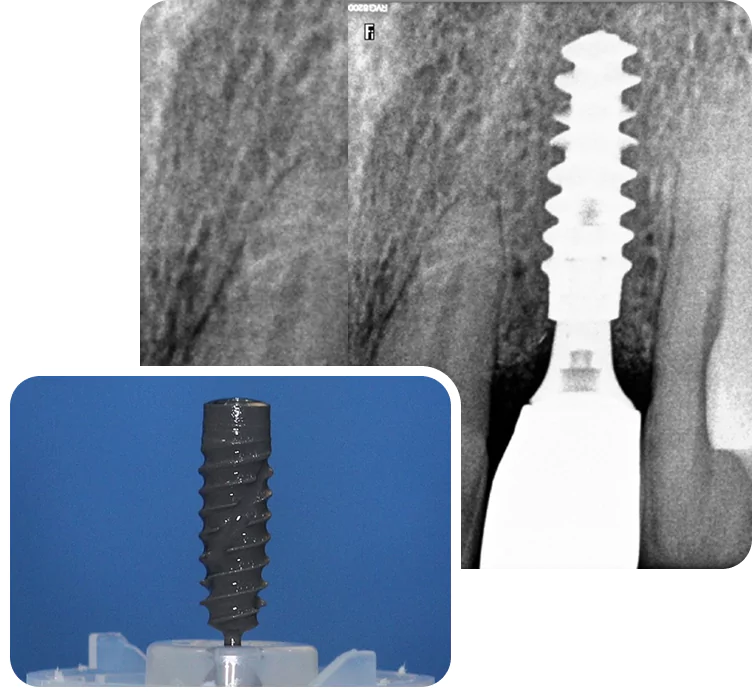

Single Tooth Implant

Single tooth implant are a simple and long-lasting way to replace one missing tooth. The implant is placed in the jawbone and acts like a root. A crown is attached on top to match the rest of your teeth. It looks real, feels strong, and helps you chew normally. Over time, it also helps prevent bone loss in that area. Unlike a dental bridge, it doesn’t rely on or damage the tooth next to it.

Single Tooth Implant at Smilex

At Smilex, we start by checking your bone and gum health with a 3D scan. Then we plan the implant placement digitally to keep it precise and safe. If the bone is thin, we’ll talk to you about grafting options before starting.

Every case is handled step by step, with clear instructions and no pressure. We take time to make sure you're comfortable and know what to expect. We use trusted implant systems and custom-made crowns that match your natural teeth.

The process doesn’t involve cutting healthy tooth, which is often needed with a bridge. Healing is usually smooth with good care. We also schedule follow-ups to make sure everything is on track. The goal is to keep things simple, honest, and long-lasting.